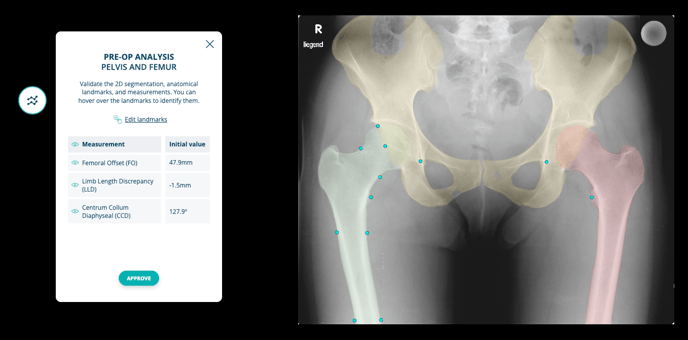

The measurements made by the procedure are displayed in the image:

- Femoral Offset (FO): The distance measured from the Anatomical Axis of the Femur (AAF) to a Hilgenreiner parallel line that runs through the center of the femoral head;

- Limb Length Discrepancy (LLD): The variation in length measured between the Lesser Trochanters’ Lines (LTL) on both sides.

- Centrum-Collum-Diaphyseal (CCD): The angle formed between the axis of the femoral shaft and the axis of the femoral neck.

- Validate landmarks and consult measurements

Upon creating the case and uploading the image, the system will automatically place all relevant landmarks, allowing you to view the pre-operative values of each measurement.

If necessary, you can refine the position of these landmarks. Simply click on "Edit landmarks," make the required adjustments, and then save your changes by selecting "Save." The measurements will be updated accordingly, enabling you to continue to the next step by clicking “Approve.”